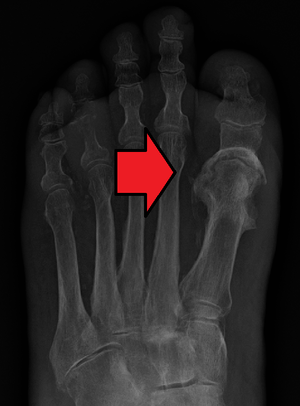

| Osteomyelitis of the 1st toe | |